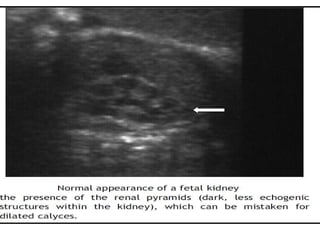

Fetal Renal Sonography Fetal kidney visualized (USG) 12-13th wk 12-40 weeks Length increases from 1.0 to 2.7 cm* APD from 0.8 to 2.6 cm Transverse diameter from 0.9 to 2.6 cm. AJR Am J Roentgenol 1991;157:545 .

Other sonographic parameters Poor corticomedullary differentiation  (lack of US visualization of the renal pyramids) Increased echogenicity  Presence of renal cysts  Perinephric urinoma